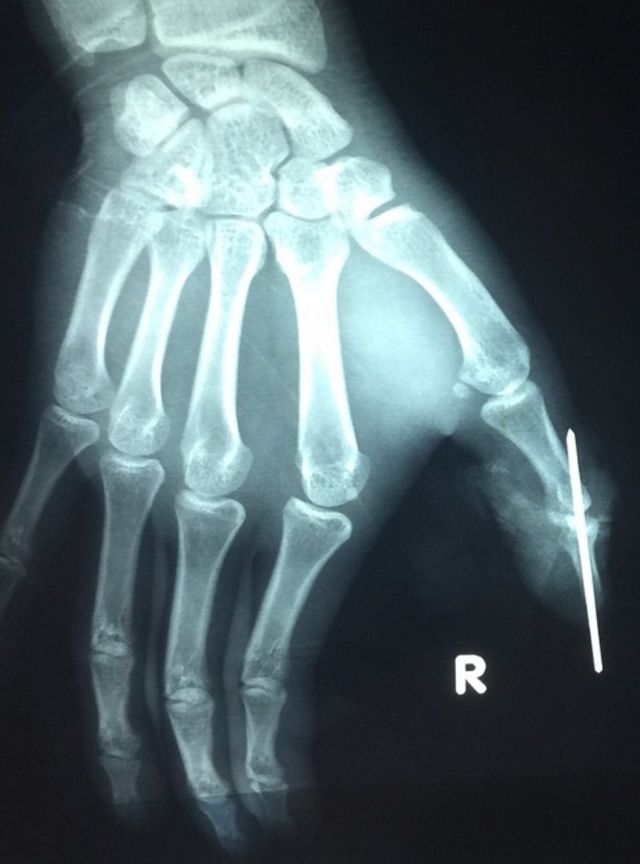

Phim chụp bàn tay bệnh nhân sau cuộc "siêu vi phẫu" - Ảnh: Dân trí. |

Các bác sĩ đã tiến hành cắt lọc hoại tử; kết hợp lại xương; dùng kĩ thuật "siêu vi phẫu" nối động mạch đốt xa ngón cái (đường kính động mạch ở vi trí này nhỏ dưới 1mm); nối thần kinh và tĩnh mạch ngón cái; nối lại gân để đảm bảo vận động cho bệnh nhân.

Sau cuộc vi phẫu, đốt ngón bị đứt lìa được tưới máu tốt, hiện ngón tay đã sống lại. Bệnh nhân được tiếp tục theo dõi để tránh nguy cơ nhiễm trùng, hoại tử. Bác sĩ nhận định sau khi bình phục, các chức năng ngón tay cái bị đứt của bệnh nhân sẽ không bị ảnh hưởng nhiều.